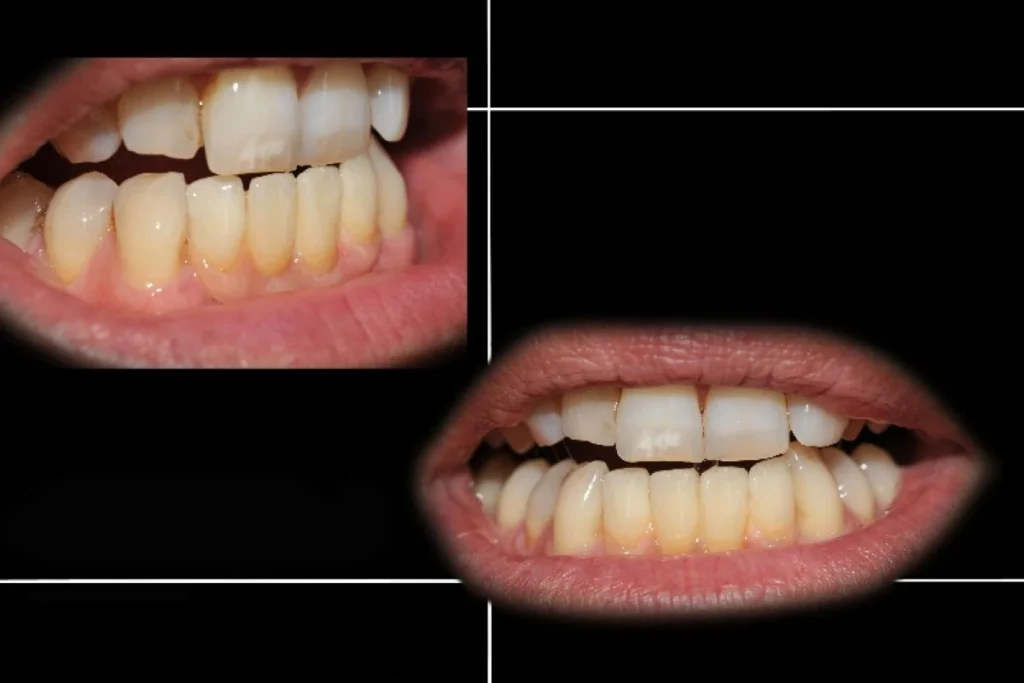

La prothèse conjointe ne se limite pas à restaurer la fonction masticatoire. Elle contribue aussi fortement à l’esthétique et au bien-être psychologique. Retrouver un sourire harmonieux redonne confiance au patient, tant dans sa vie personnelle que professionnelle.

Nous attachons donc une attention particulière à l’intégration esthétique de chaque prothèse. La forme, la teinte et la translucidité sont soigneusement étudiées pour s’harmoniser avec les dents naturelles et offrir un rendu discret et naturel.

Découvrez nos cas cliniques

La prothèse conjointe est une solution incontournable pour restaurer dents, sourire et confiance. Elle représente un équilibre entre fonction, confort et esthétique.